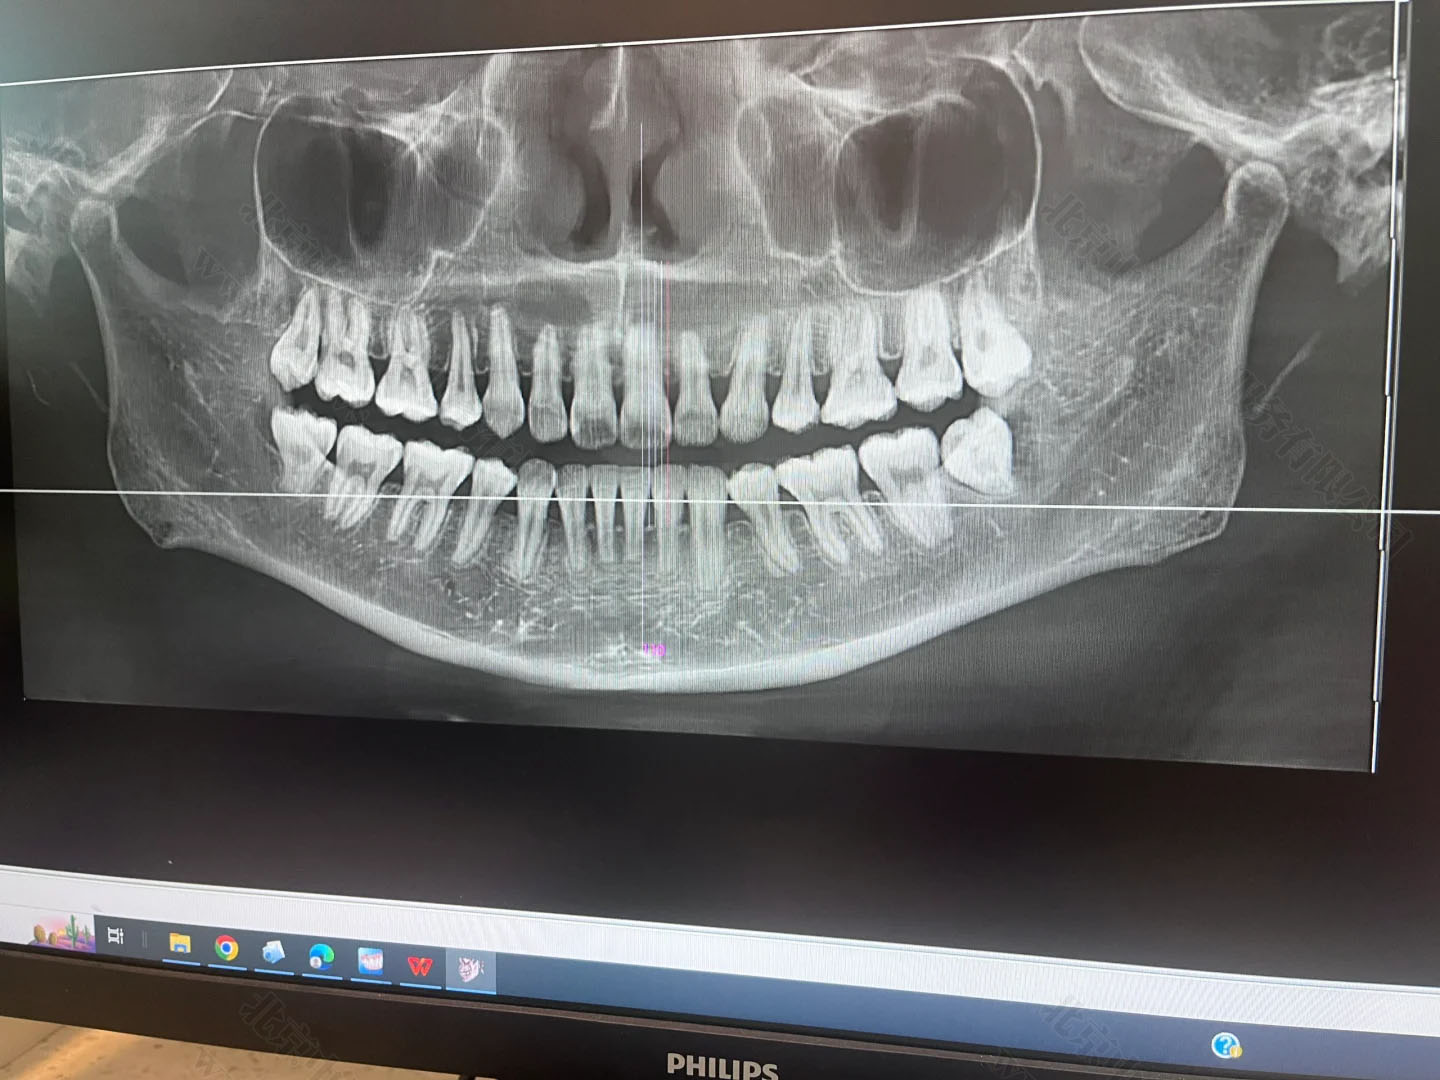

只要是裝了牙片機(jī),不管是常規(guī)拍片還是全景片,這類設(shè)備都屬于放射類診療儀器,必須先提交項目的放射防護(hù)預(yù)評價報告,也就是確認(rèn)這個設(shè)備對人有沒有輻射危害,能不能安裝和使用。

在施工前,這個報告必須提前交到北京市衛(wèi)生部門審核。審批通過了才能動工裝修,否則一切都白忙活。牙片雖然是“輕放射”,但防護(hù)的流程跟CT、核磁一樣,不能跳過。

項目完工后也不是馬上就能拍牙片,還得請專業(yè)機(jī)構(gòu)做一個職業(yè)病危害控制效果評價,就是看你這機(jī)器在使用過程中,周邊有沒有多余輻射,會不會對醫(yī)生、患者和旁人造成傷害。做完后,還得向衛(wèi)生部門提交設(shè)備驗收申請,包括檢測報告、施工資料等一整套材料。

只有經(jīng)過這道驗收關(guān),診所才可以拿到《放射診療許可證》,正式開展拍片業(yè)務(wù)。這個流程平均要花上兩三個月,不提前準(zhǔn)備就容易耽誤診所開張。